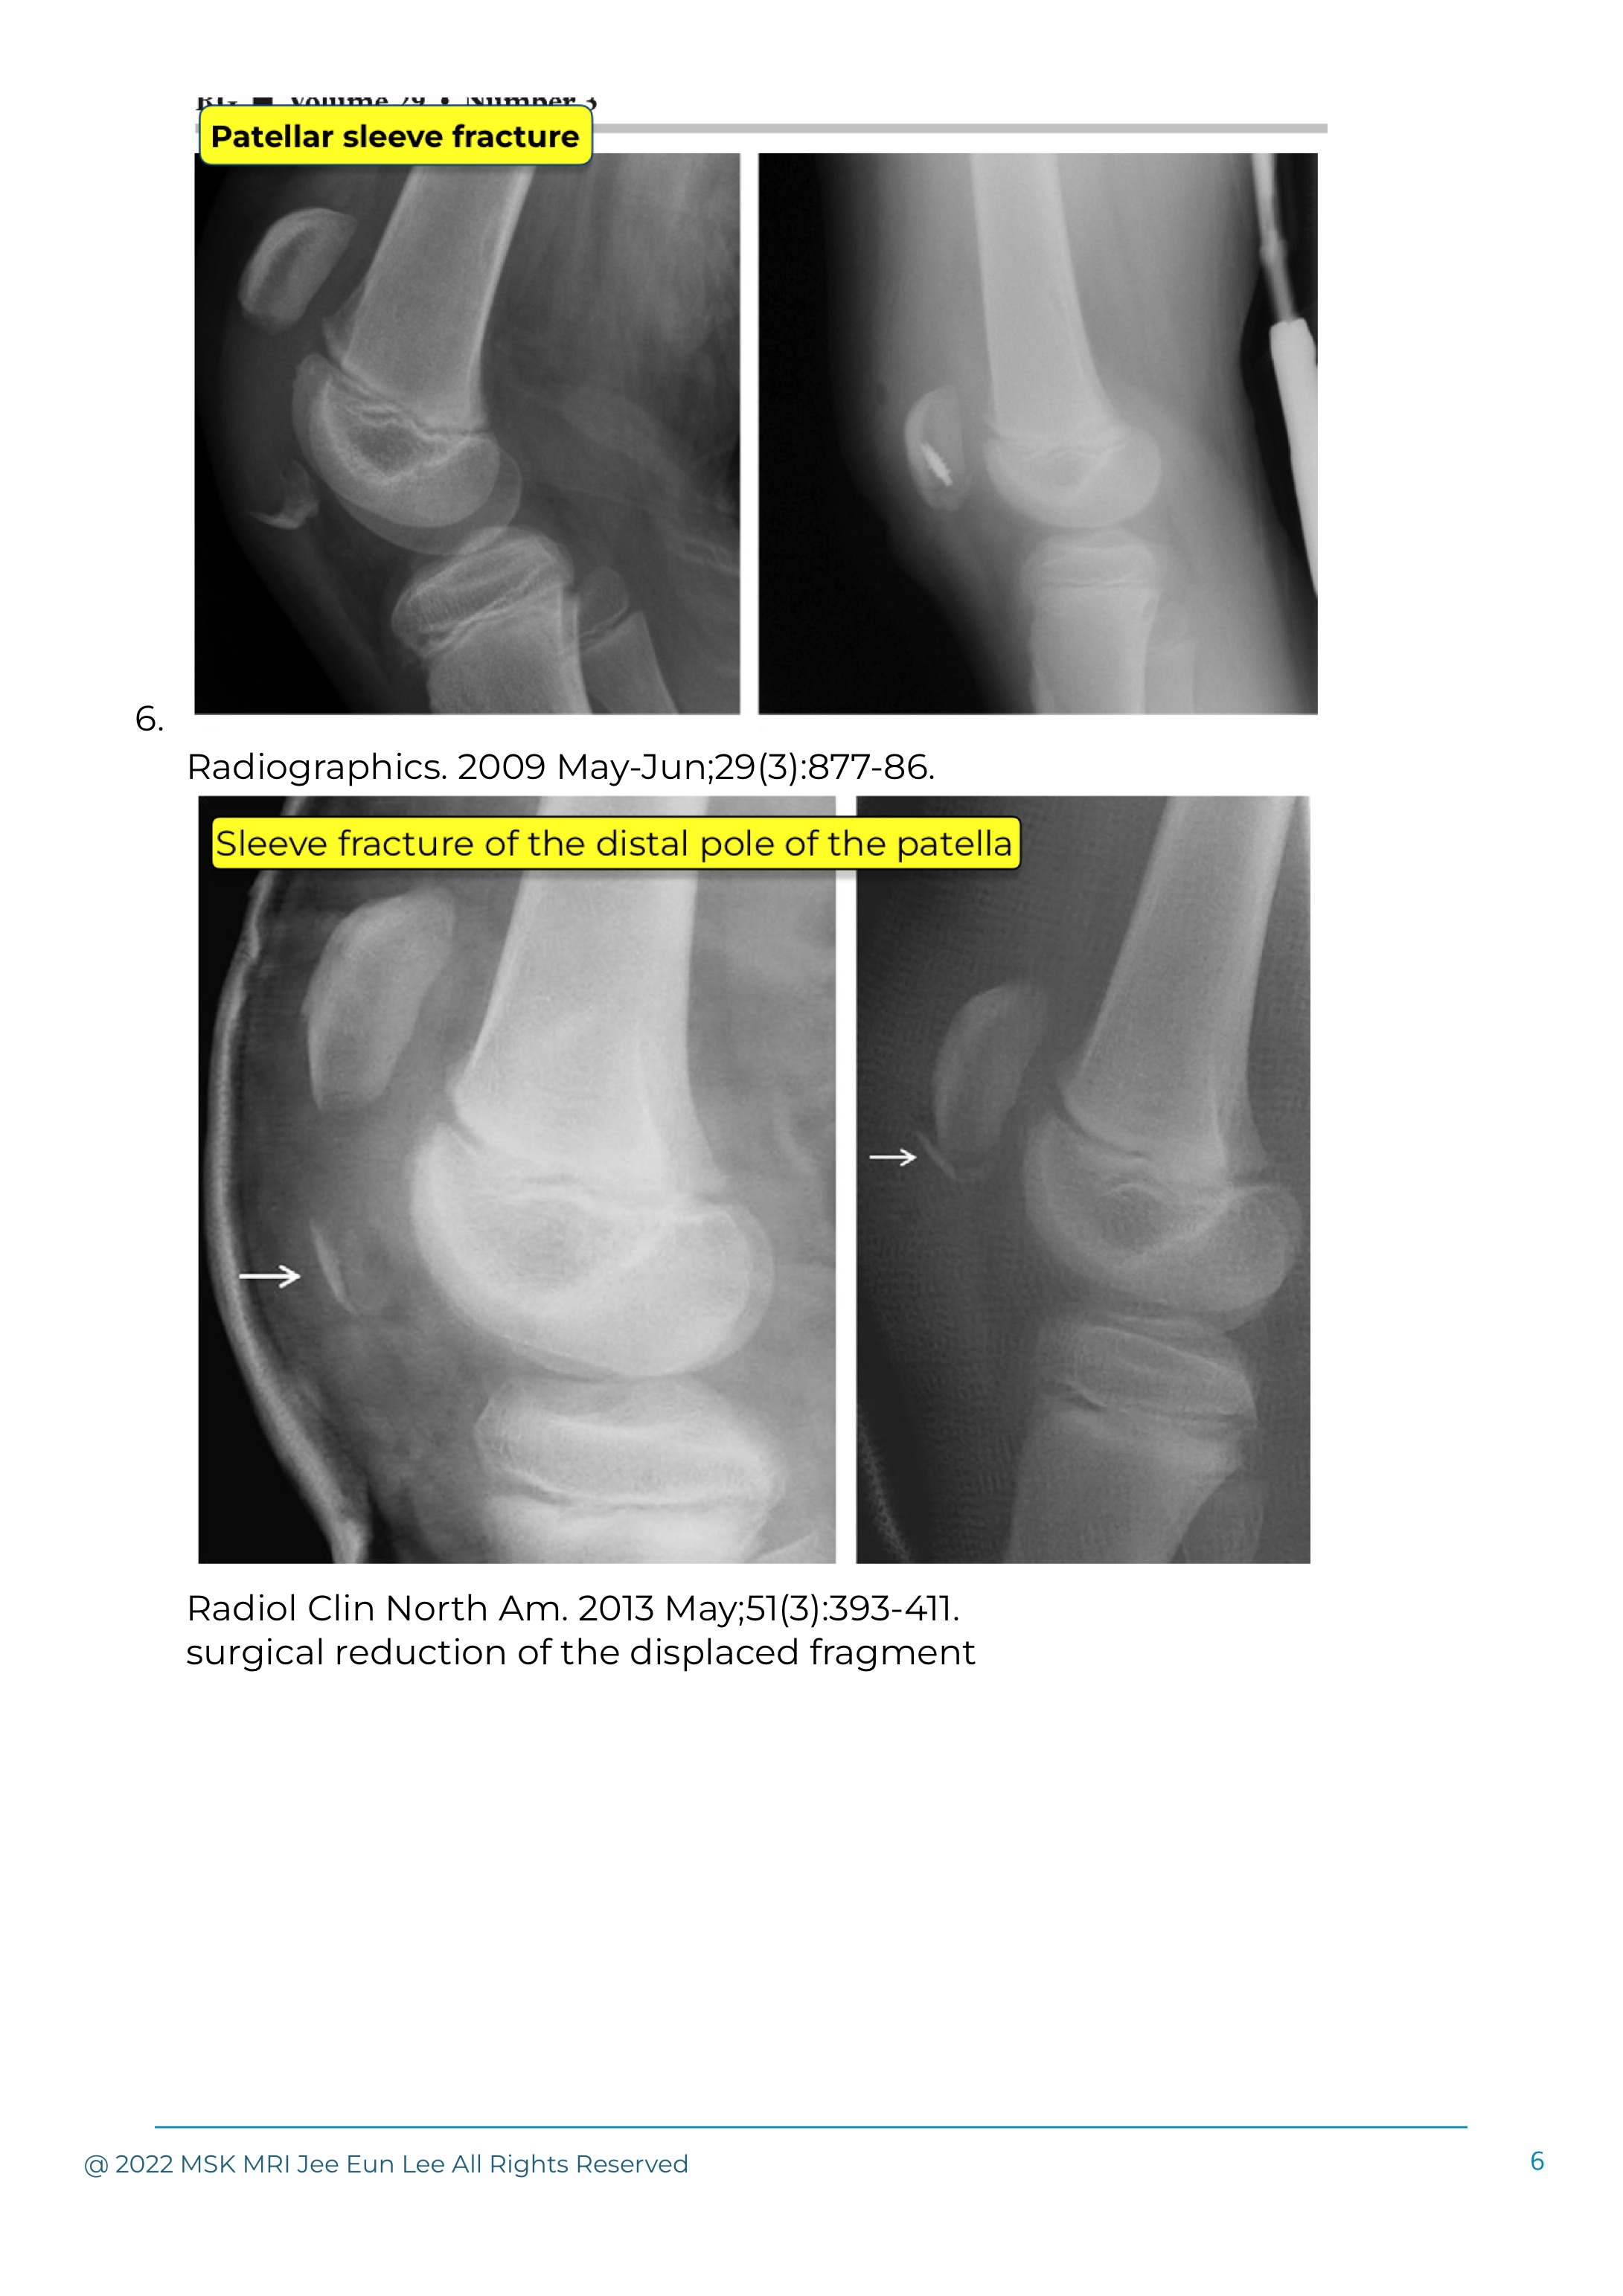

Patellar sleeve fractures are unique to the pediatric population and are most commonly seen in the 8- to 12-year-old age group.

Avulsion of the inferior pole of the patella is a fracture seen predominantly in the immature skeleton and is often termed a ”sleeve fracture,” because a sleeve of unossified cartilage and bone is stripped off the lower pole of the patella.